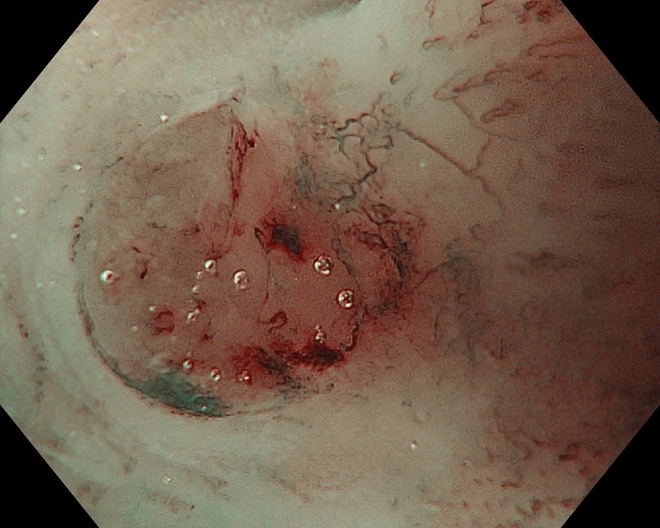

Một bệnh nhân 63 tuổi đã được phát hiện ung thư thực quản giai đoạn sớm nhờ công nghệ này và điều trị thành công, xuất viện sau 2 ngày.

Trong một trường hợp khác, bệnh nhân 67 tuổi được phát hiện tổn thương qua nội soi công nghệ cao. Tuy nhiên, qua đánh giá chuyên sâu, bác sĩ xác định tổn thương đã vượt chỉ định điều trị nội soi và chuyển sang phẫu thuật.

Kết quả mô bệnh học sau đó xác nhận ung thư đã xâm lấn dưới niêm mạc, phù hợp với chỉ định ngoại khoa.

Hình ảnh tổn thương thực quản của bệnh nhân.

Thực tế này cho thấy vai trò quan trọng của nội soi công nghệ cao kết hợp với kinh nghiệm lâm sàng trong việc đánh giá chính xác giai đoạn bệnh, từ đó đưa ra phương pháp điều trị phù hợp, tối ưu.